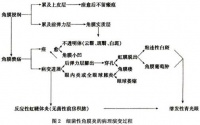

病程[编辑 | 编辑源代码]

一、炎症初起[编辑 | 编辑源代码]

当炎症初起时,在角膜组织内就有或多或少的刺激原和游动细胞形成浸

润,同时角膜组织充满液体,因而患处肿胀而混浊,甚至有时高出表面,即所谓角膜浸润阶段。

二、角膜浸润[编辑 | 编辑源代码]

角膜浸润: 其主要症状为灰黄色混浊、阴暗、无光泽,高出角膜表面。

三、进行性角膜溃疡[编辑 | 编辑源代码]

进行性角膜溃疡: 角膜浸润的进展结局有二:

a.浸润被吸收。当角膜浸润尚未达到最高峰时,炎症现象即消退,角膜光泽恢复,完全透明(这种结局在临床不多见)。

b.浸润化脓。一般的情况是,角膜组织被感染后迅即溶解,上皮细胞甚至

实质浅层由于坏死而脱落,遂形成溃疡。溃疡边缘初则较为混浊,继则中部及其周围进一步恶化。溃疡基底呈灰色,不平坦,边缘不清,即所谓不洁期或进行性的溃疡。进行时,溃疡可向一侧或周围扩展;也可向深层进展,或向周围或深层同时进展。例如淋病性角膜溃疡就是这样,它不但向角膜周围,同时也向深层进展,穿破角膜,甚至破坏角膜全部。

四、退行性角膜溃疡[编辑 | 编辑源代码]

退行性角膜溃疡: 最常见的角膜溃疡为局部坏死、部分脱落,其未脱落部分仅与基底的中心相连接。这种情况表明毒素集中于溃疡中部,其外围已被多核白细胞所包围。这些白细胞吞噬细菌、溶解坏死组织。这时溃疡周围的上皮细胞速即向溃疡中心进展,上皮细胞的增生和伸展非常迅速(通常角膜上皮细胞刮去后24小时内即可完全恢复),同时溃疡的坏死部分继续脱落,直至溃疡的混浊逐渐减轻消失。溃疡的基底及其边缘趋向平滑、透明、而进入洁净期。这就是退行性阶段。

五、角膜瘢痕[编辑 | 编辑源代码]

角膜瘢痕: 当角膜溃疡达到洁净期后,角膜内结缔组织增生,修复缺损,溃疡愈合,形成瘢痕。溃疡小而浅仅累及上皮细胞层者,角膜可以完全恢复透明。如果前弹力膜和角膜实质浅层受累,则遗留致密混浊的瘢痕。混浊初则暗淡,继则浓度增加,但永远不会越过溃疡边缘。角膜瘢痕的消失仅限于乳儿,年龄稍大则不可能,必然遗留永久的瘢痕,从而引起视力障碍。在瘢痕开始形成而被破坏部分尚未完全恢复原来的弯曲度,但荧光素已不着染,角膜上形成一小凹,名为角膜小面。最终小面消失,角膜恢复正常的弯屈度。但也有个别病例的角膜小面永久不变。

角膜瘢痕的大小和厚薄按溃疡轻重而有所不同,薄者混浊浅在,名角膜云翳,稍厚者名角膜斑翳,最厚而致密者名角膜白斑。